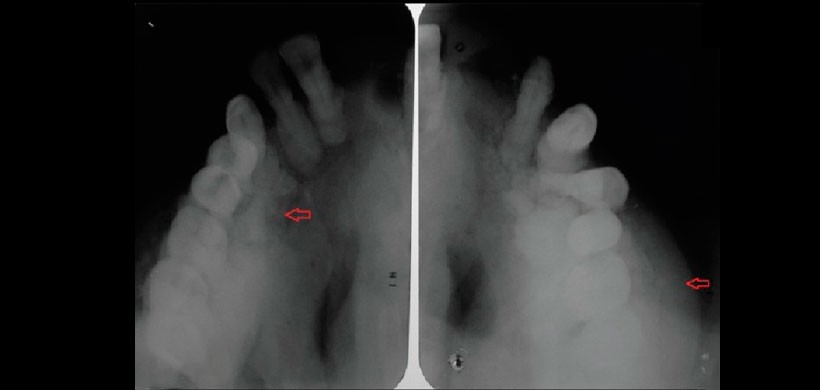

Fig 1. Radiografía oclusal lateral que muestran osteosclerosis y un aspecto de copos de algodón.